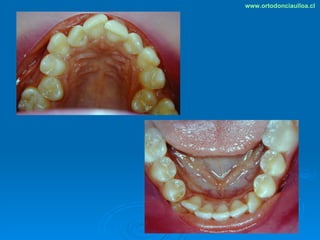

Este documento presenta dos casos clínicos de pacientes que recibieron tratamiento de ortodoncia. El primer caso fue de una paciente femenina de 14 años con apiñamiento dental y mordida cruzada que fue tratada mediante extracción de premolares y alineamiento dental. El segundo caso fue de un paciente masculino de 14 años con clase II esqueletal y desarmonía dentomaxilar que fue tratado con extracción de premolares y corrección de mordida. Ambos casos mostraron mejoría después de 3 años de tratamiento.